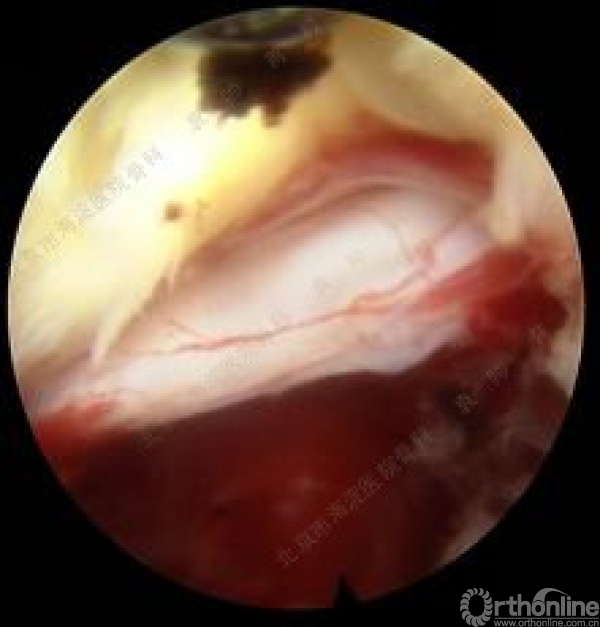

优先处理近端间隙,尤其是近端椎间盘突出的较大时或脱垂超过椎弓根平面者,有累及囊内未发出的下位神经根可能,即一个椎间盘引发多个神经根症状。如果近端间隙处理后患者症状缓解彻底,对远端间隙可不予处理,减少病人创伤的同时也能减少医生的X线暴露。操作时于穿刺点应用1%利多卡因局部麻醉,透视下穿刺至病变节段下位椎体上关节突尖部,置入导丝后扩张管道逐级扩张,依据不同扩张管道应用配套环锯或骨钻磨除上关节突腹侧部分骨质直至椎管外边界,置入工作管道,确定工作管道位于椎管内,置入内窥镜探查。如果关节突骨性结构仍对神经根显露构成阻碍,内镜监视下动力磨钻对其适度扩大,切除部分外侧纤维环及黄韧带后探查神经根并摘除致压物。术中神经根周围减压时如出现神经根激惹现象,及时询问患者能否复制术前疼痛。完成一个间隙减压后询问患者疼痛及麻木缓解程度,并配合神经根牵拉试验检查手术效果,如患者仍感症状未完全缓解,拔出内镜及管道再次行远端间隙手术。手术结束后缝合伤口,再次询问患者神经症状缓解情况并再次行神经根牵拉试验证实手术效果。